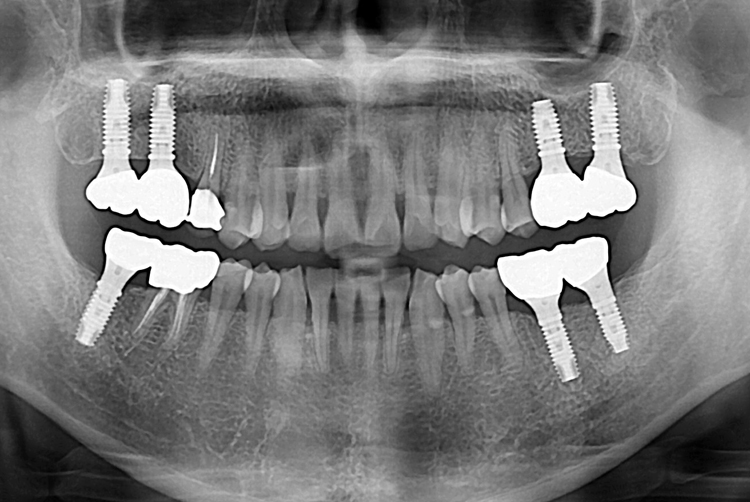

[임플란트] 어금니 임플란트

치료후 : 2017-11-17

세종치과는 많은 환자와 다양한 케이스를 바탕으로

항상 편안한 임플란트 수술을 제공하고자 노력하고,

오래동안 튼튼히 쓸 수 있는 임플란트 수술을 가장 큰 목표로 삼고 있습니다.